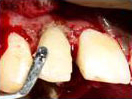

A case of combined REP in one Root and VPT in another Root.

Wound in bone (marked) in one root has healed through REP which is revealed in 6 and 12 months follow up IOPAR, the unaffected pulp in another Root Canal is protected through VPT resulting in the maintenance of validity of Tooth.